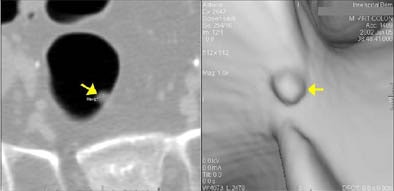

| The same 5-mm sessile rectal polyp is clearly depicted in the 2-D axial view (left) and in the 3-D endoscopic view (right). Images courtesy of Dr. Hanno Hoppe. |

Virtual colon dissection (VCD) achieved 78% sensitivity for the detection of lesions 10 mm and larger, compared with 95% for axial viewing with 3-D problem-solving. For all lesions smaller than 10 mm, sensitivity was 50% for VCD and 42% for axial reading with 3-D problem-solving.